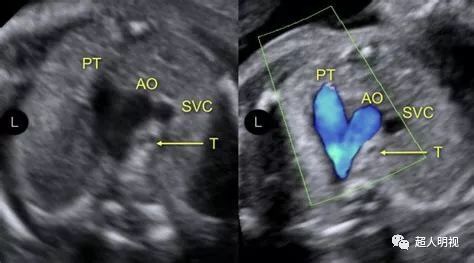

三血管-气管切面可见畸形

三血管气管切面异常